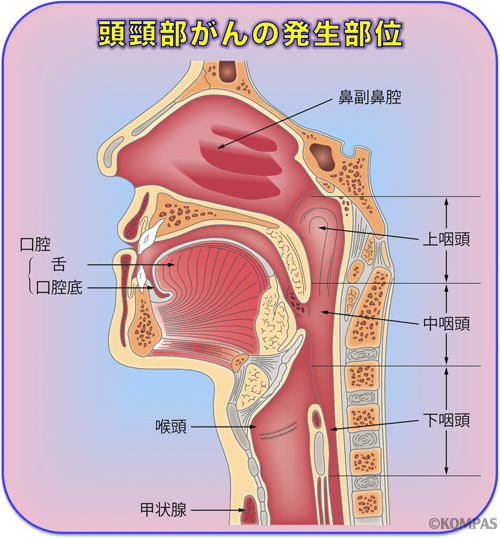

中咽頭癌 ct. 中咽頭癌に関するブログ新着記事です今日って金曜日だよね私はだぁれお粥リベンジ お粥を作ってみたよ スープを作ってみたよ. Ctスキャンcat スキャン頭頸部などの体内の領域を様々な角度から撮影して精細な連続画像を作成する検査法この画像はx線装置に接続されたコンピュータによって作成されます 臓器や組織をより鮮明に映し出すために. 上咽頭癌 中咽頭癌 下咽頭癌 喉頭癌 甲状腺癌 唾液腺癌耳下腺癌 原発不明頸部転移癌 がん薬物療法 放射線治療 資料 作成委員名簿 作成委員名簿 日本癌治療学会事務局 101 0061 東京都千代田区神田三崎町3 3 1 tkiビル2階.

頭頸部癌 最近の診断 治療の進歩 耳鼻咽喉 頭頸科 順天堂医院